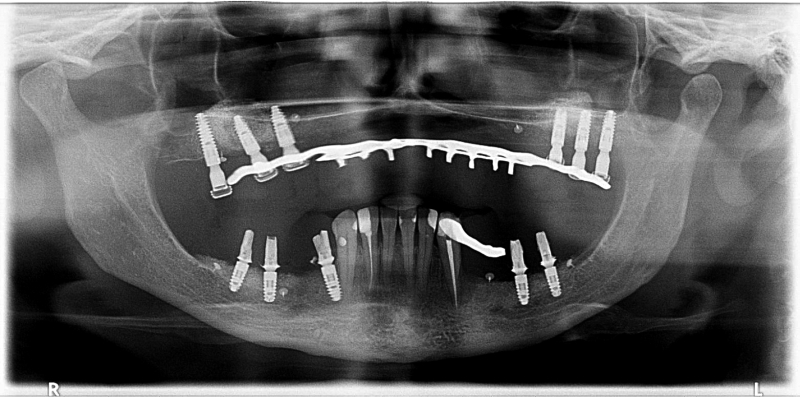

18/18 - X-ray scan 9 months post-op: Full integration of maxgraft® bonering and implants and proceeding remodeling of the grafts

Vertical augmentation & sinus lift with maxgraft® bonering - Dr. O. Yüksel and Dr. B. Giesenhagen